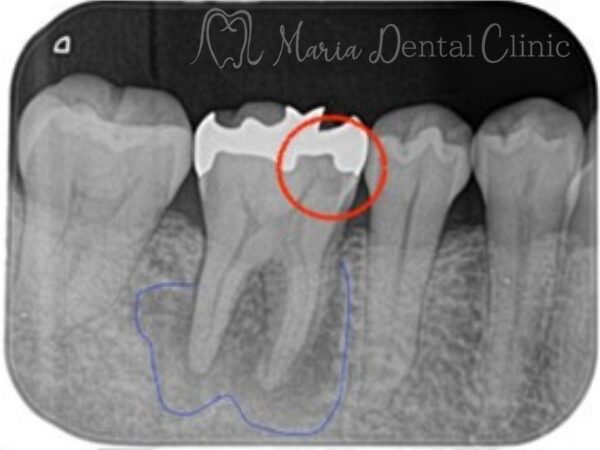

赤矢印は2次虫歯部位を指す

画像2の赤丸部分には被せ物直下に黒く写る黒い影は2次う蝕(2次カリエス)を強く疑うレントゲン写真でした。

マイクロスコープで治療を開始した際に同部位を確認すると、歯科充填材料の下に広がる虫歯を確認し、通法通りのコンセプトに基づき精密根管治療を施しました。